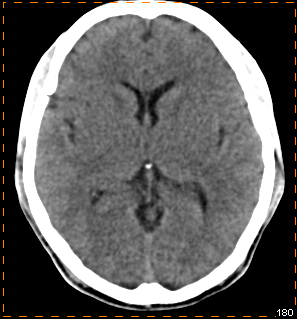

脑部多巴胺受体显像辅助诊断帕金森病

患者,男性,35岁

临床怀疑帕金森病

我科使用11C-CFT进行脑部多巴胺受体显像

PET/CT示:

双侧尾状核、双侧壳核放射性摄取对称,未见明显减低

根据PET图像,最终排除帕金森病